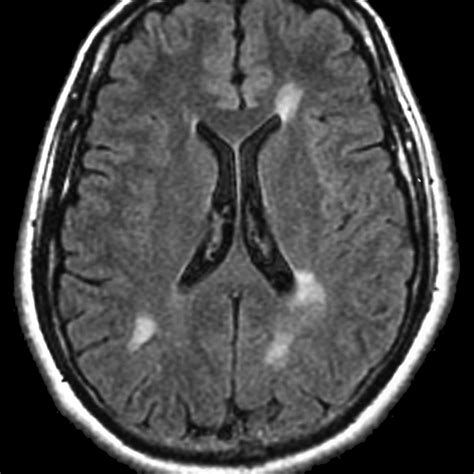

• Neurological assessments: It is frequently used to identify multiple sclerosis plaques or brain tumors.

The primary purpose of adding a contrast agent during your scan is to improve the visibility of internal structures. Without contrast, some tissues may appear similar in density, making it difficult for a physician to identify subtle abnormalities. By using a contrast agent, the substance travels through your blood vessels and accumulates in areas of increased blood flow, such as tumors, areas of inflammation, or damaged blood vessels. This “enhancement” makes these areas appear brighter or more defined on the resulting images.

After the scan is complete, the images are sent to a radiologist. They analyze the scan to compare the non-contrast and contrast-enhanced images. The “enhancement” patterns allow the radiologist to write a detailed report for your primary physician. This report usually outlines findings in clinical terms, noting the presence or absence of abnormalities. It is important to remember that the MRI report is just one part of your diagnostic puzzle; your doctor will correlate these results with your physical exam and other lab findings to finalize a diagnosis and treatment plan.